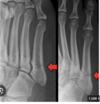

Lisfranc injury findings on xray

• Midfoot injury - tarsometatarsal fracture dislocation

• High risk for compartment

• Axial load on plantarflexed foot

• Ortho, back slab, NWB